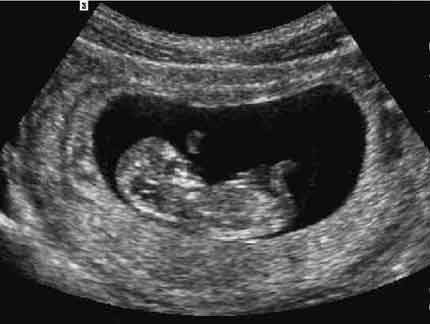

Fetal profile 1st trimester

Note: Images are shown for illustrative purposes. Do not attempt to draw conclusions or make diagnoses by comparing these images to other medical images, particularly your own. Only qualified physicians should interpret images; the radiologist is the physician expert trained in medical imaging.